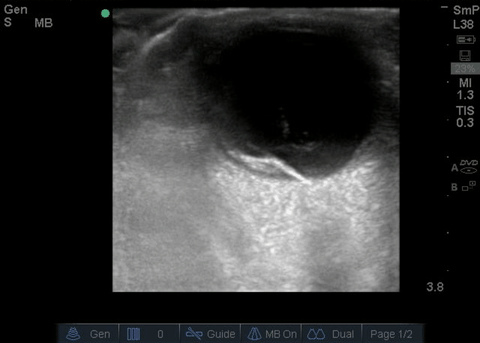

Vitreous and retinal detachment

Courtesy of Shirly Wu, MD - UCONN EM Residency